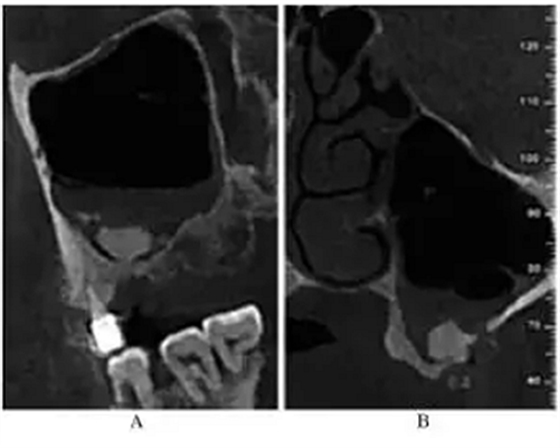

CBCT示:左侧鼻甲水肿,左侧上颌窦内可见黏膜呈半圆形隆起,密度均匀升高,未见钙化及明显骨质破坏;26牙剩余牙槽突高度(residual bone height,RBH)1.8mm,27牙RBH4.2mm,28牙RBH11mm,上颌窦颊侧骨壁厚度约1mm(图1)。

图1 术前CBCT

注:A,矢状面;B,26颊舌向切面;C,27颊舌向切面;D,28颊舌向切面。